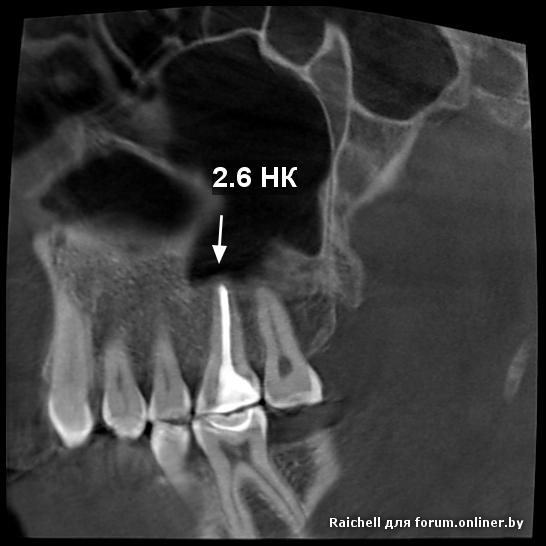

Во всех депульпированых зубах есть проблемы, плюс в пазухе слева от 25 зуба есть нюанс

16,15 на удаление, потом синус и имплантация Все зубы перелечила. это кт до лечения. Сейчас под временными коронками. Предлагают имплантацию 1.5,2.5 и 4.5 (убрать мост, т.к. 4.6 сильно разрушен). 1.5 удалить и сразу же имплант, но про наращивание не говорили.

inycik:Во всех депульпированых зубах есть проблемы, плюс в пазухе слева от 25 зуба есть нюанс

16,15 на удаление, потом синус и имплантация

Все зубы перелечила. это кт до лечения. Сейчас под временными коронками. Предлагают имплантацию 1.5,2.5 и 4.5 (убрать мост, т.к. 4.6 сильно разрушен). 1.5 удалить и сразу же имплант, но про наращивание не говорили.

А скажите, что в пазухе? Это как-то повлияет на имплантацию